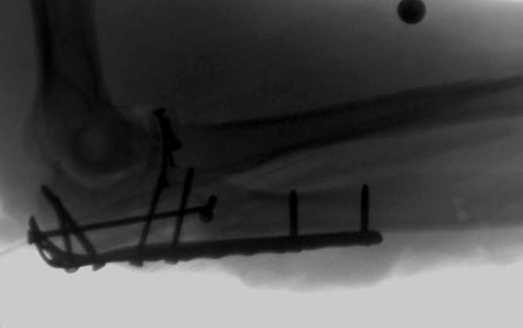

Здесь выставлены несколько случаев и варианты фиксации локтевого отростка, некоторые в комбинации с другими переломами.

1 вариант применен ACUMED локинг пластина

2 вариант

перелом локтевого отростка с переломом головки лучевой кости (использованы 2 мм шурупы)